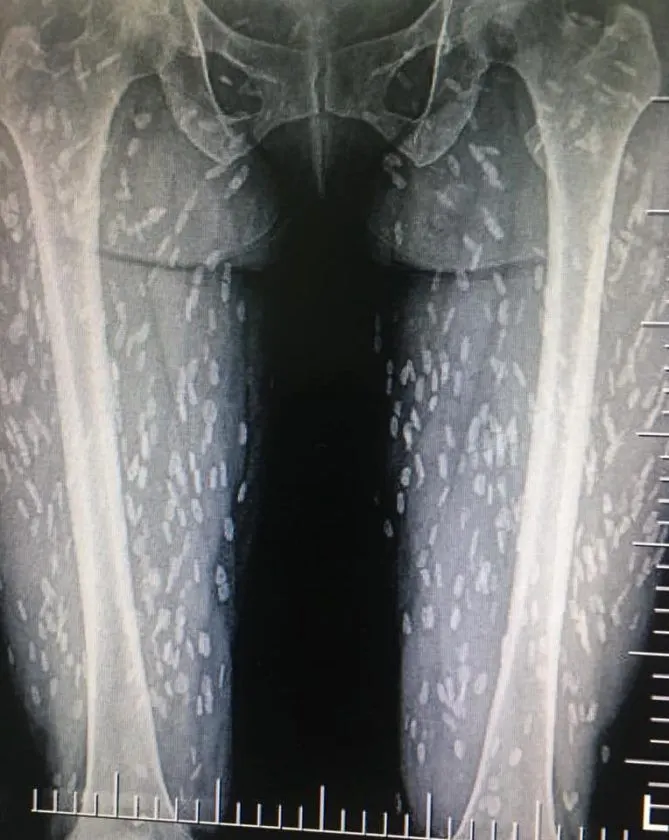

จากภาพทางด้านล่างคือ x–ray ตรงขา สะโพก แล้วที่ขาวๆ ที่กระจายทั่วกล้ามเนื้อ คือตัวอ่อนพยาธิตืดหมูที่ไชเข้าสู่ร่างกายแล้วระบบภูมิคุ้มกันของร่างกายก็รับมือกับมัน จนเกิดหินปูนมาเกาะ เคยเห็นแต่ในตำรา หมอเจ้าของโพสต์ได้เจอของจริงจะๆเลย

ส่วนสาเหตุเกิดจากการกินเมนูที่ใส่หมูดิบแล้วมีตัวอ่อนพยาธิในนั้น หรือกินผักที่ปนเปื้อนไข่ของพยาธิชนิดนี้ แล้วพอตัวอ่อนมันไชเข้าร่างกาย ก็จะไปแถวกล้ามเนื้อมั่ง หรือเข้าสมอง จากนั้นก็จะกลายเป็นหินปูนแบบที่เห็นแล้วทำให้เกิดอาการต่างๆนานา บางคนที่ไชเข้าสมอง ก็จะไปหาหมอด้วยอาการ ปวดหัวเรื้อรัง ชักเกร็ง